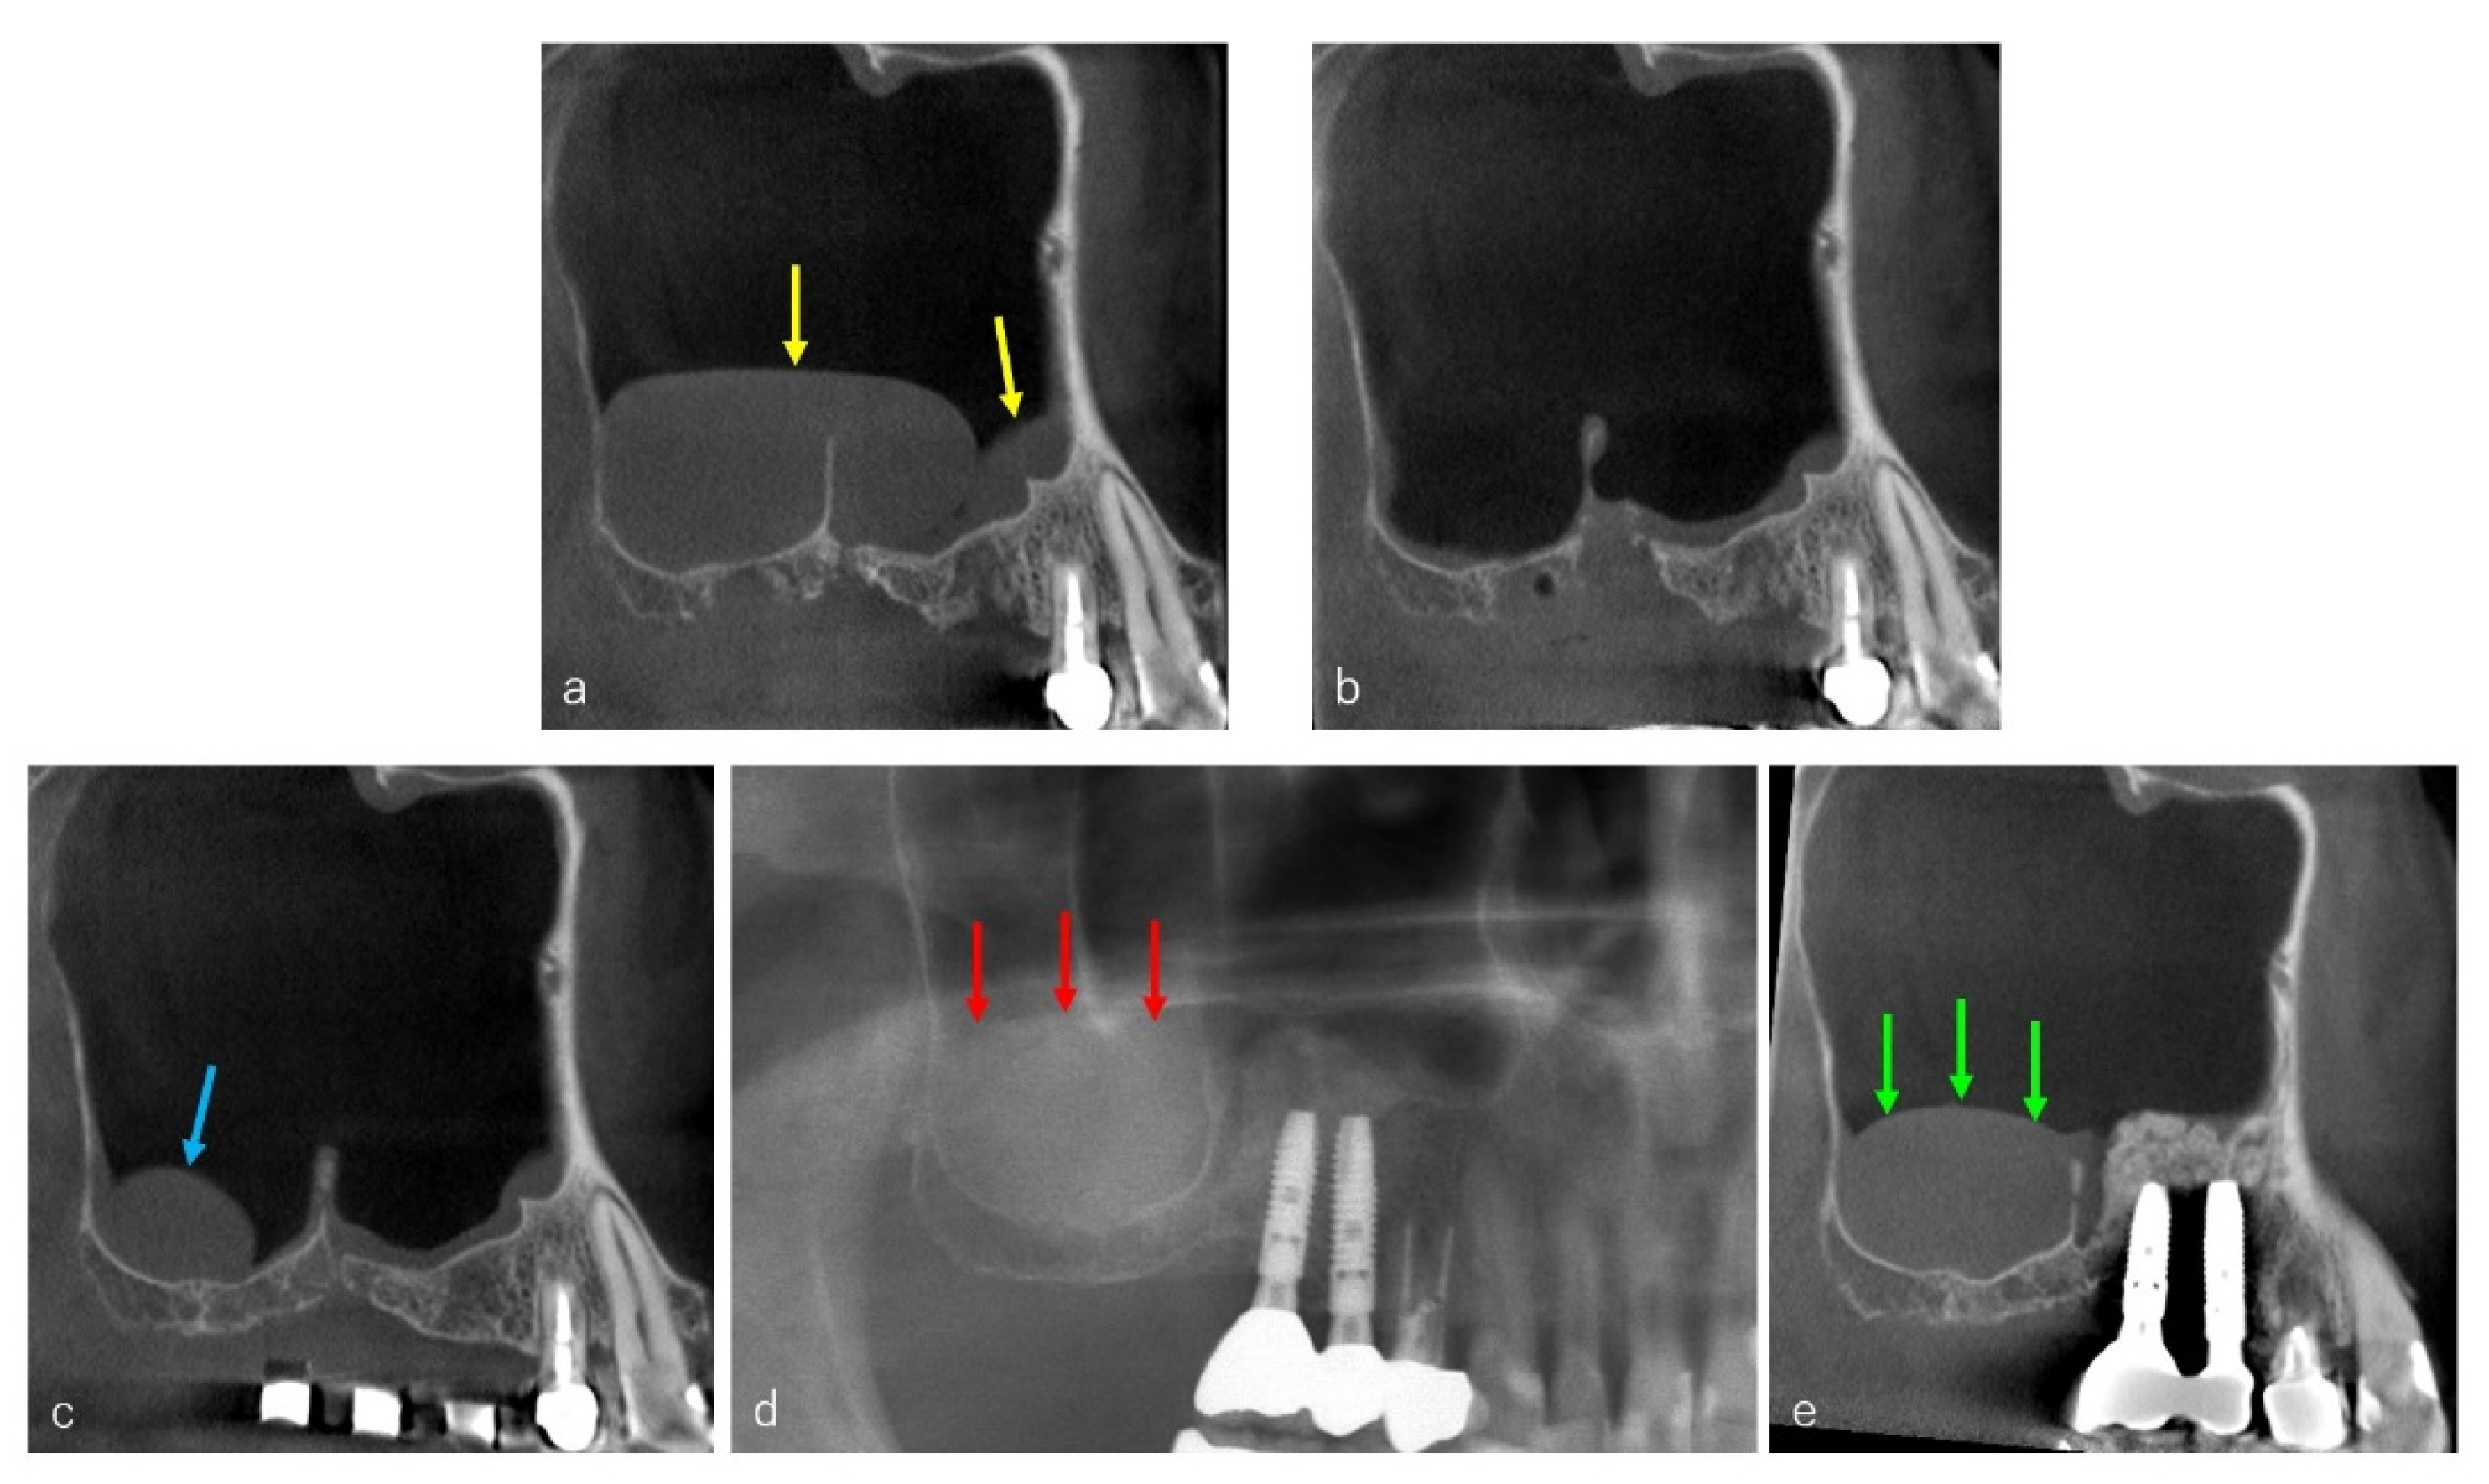

2.2. CBCT Evaluation

3. Results

3.2. CBCT Evaluation of the Cystic Lesions

3.5. Surgery and Clinical Progress